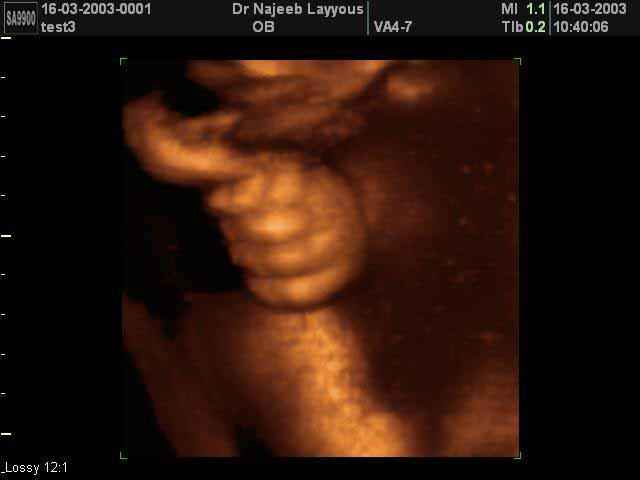

3D Ultrasound Scan Photos of Fetal Limbs | Dr N Layyous

3D Fetal Limbs Ultrasound Scan Photos